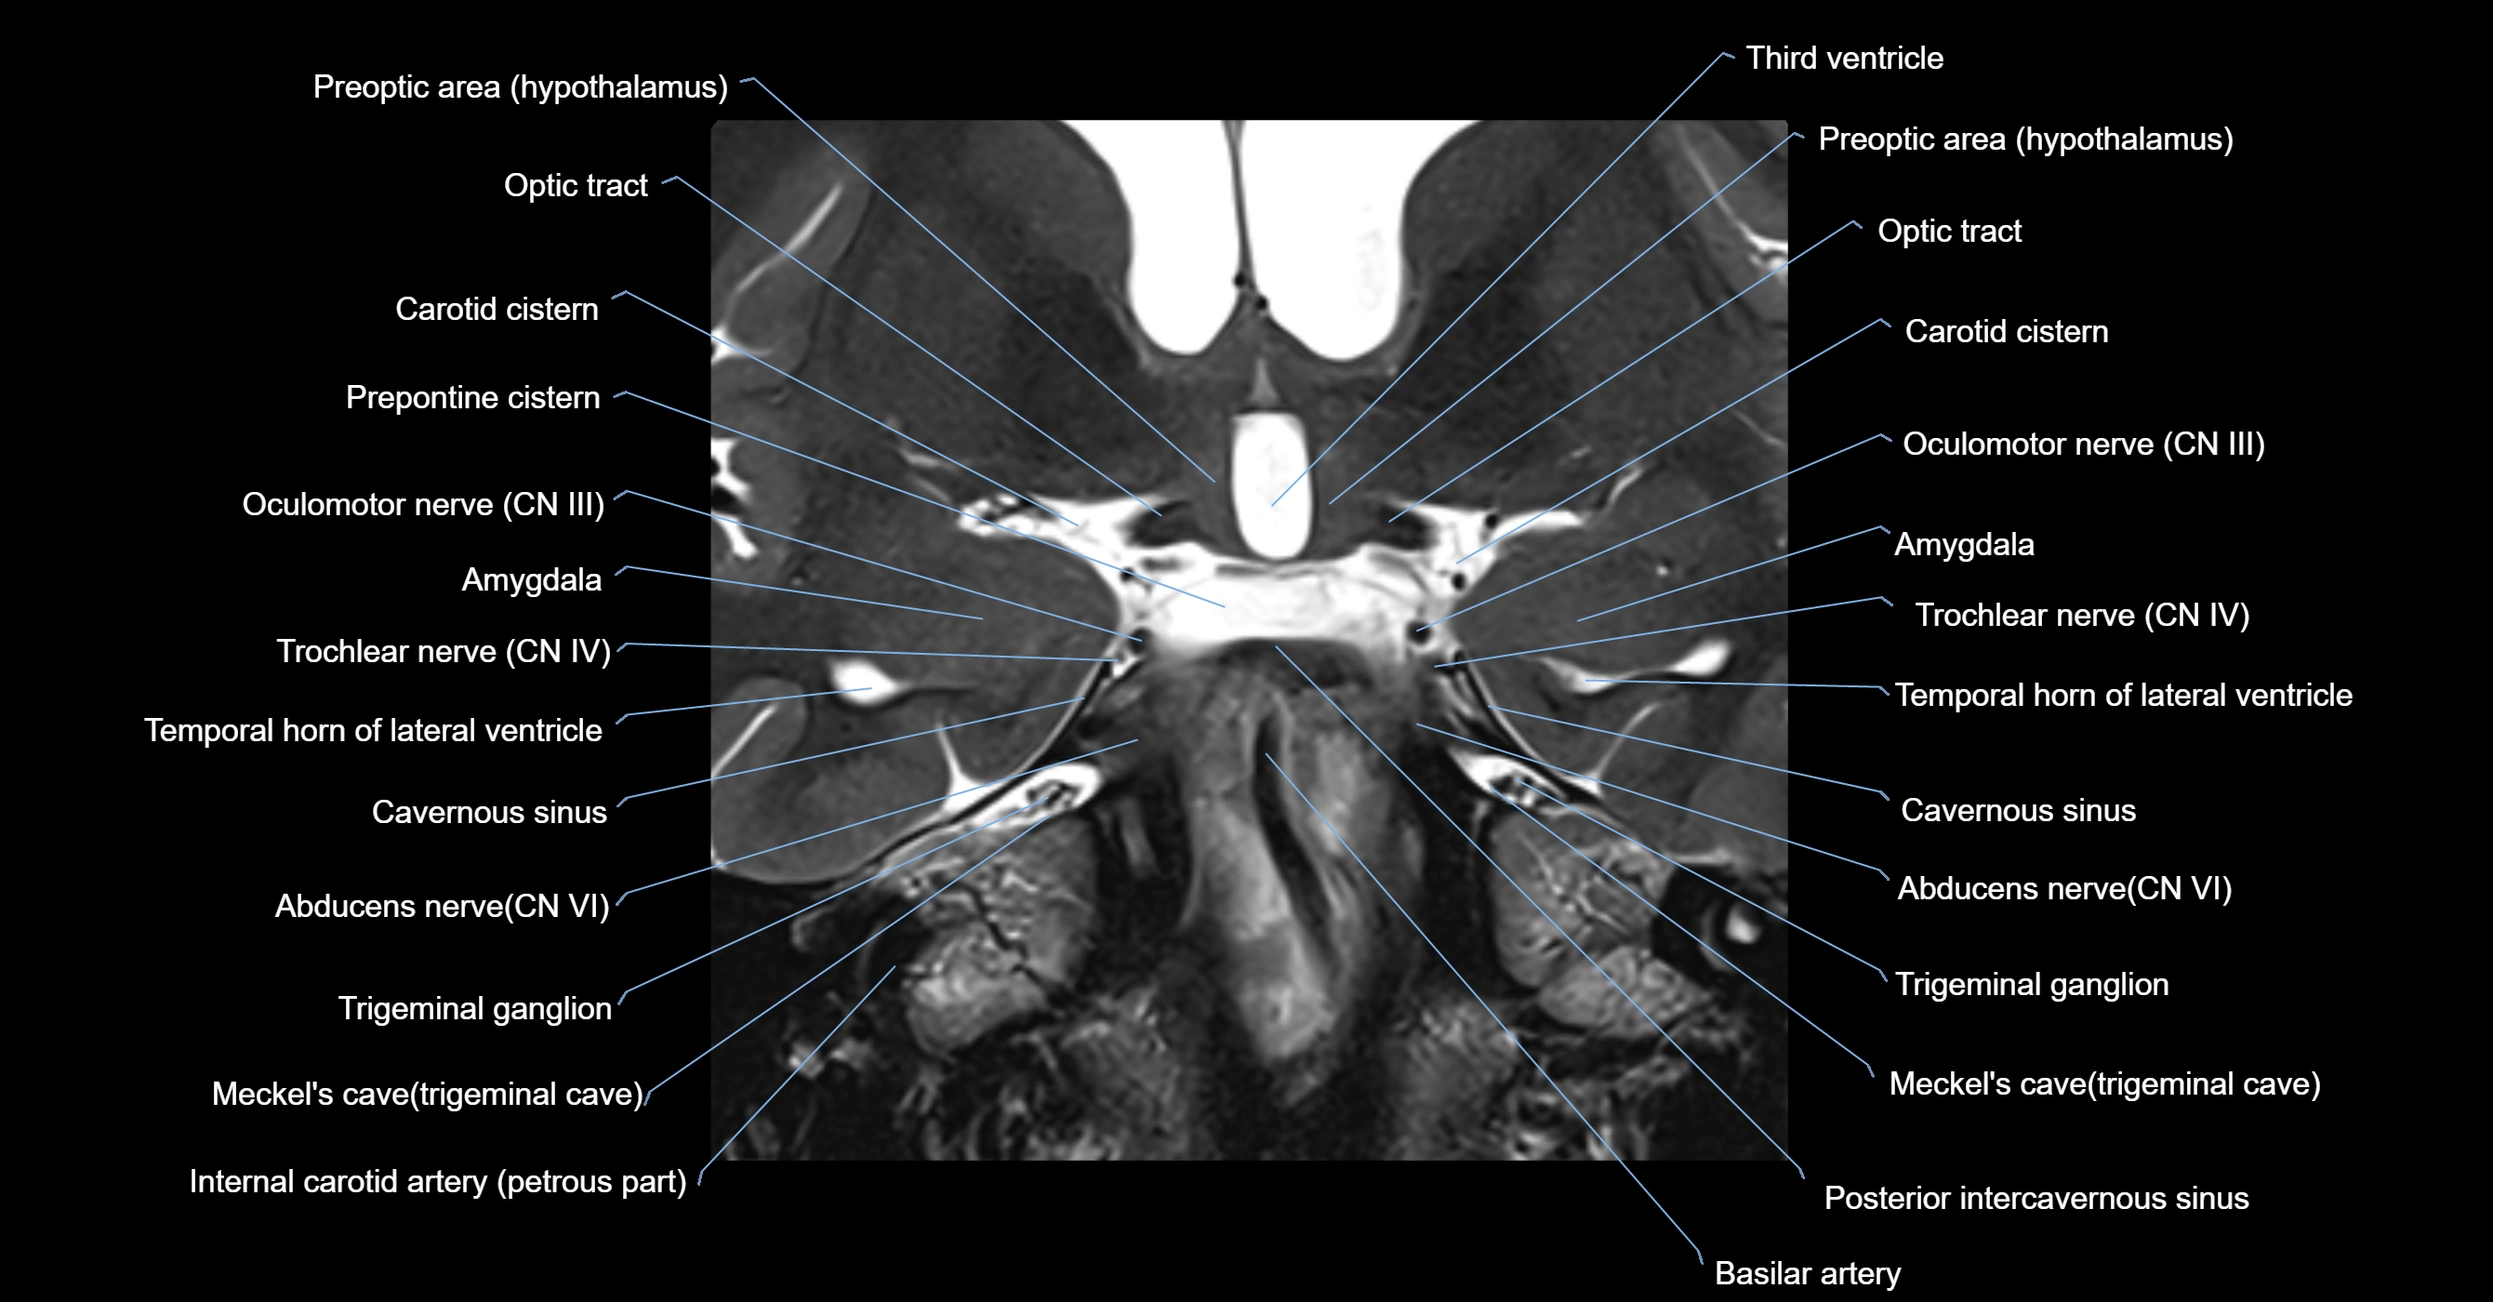

MRI Appearance

-

The abducens nerve is a small, thin, linear structure

Best visualized on high-resolution T2-weighted 3D MRI sequences (e.g., FIESTA or CISS)

Seen as a hypointense (dark) line running from the brainstem at the pontomedullary junction, traversing the prepontine cistern, and entering Dorello’s canal under the petrosphenoidal ligament, then into the cavernous sinus, and finally the orbit

May be challenging to visualize in standard MRI due to its small size

Pathology may be inferred by absence, displacement, or enhancement of the nerve

MRI images